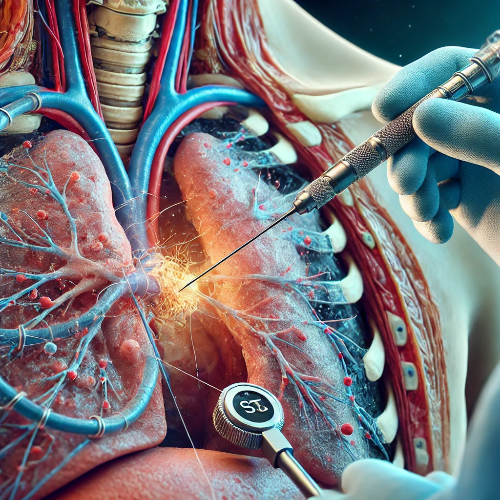

경피 바늘 조직검사

- 경피 바늘 조직검사는 CT나 초음파를 이용해 폐에 바늘을 삽입하여 조직을 채취하는 방법으로, 주로 폐의 중심부에 위치한 종양을 확인하는 데 사용됩니다. 이 검사는 진단 정확도를 높이는 데 중요합니다.